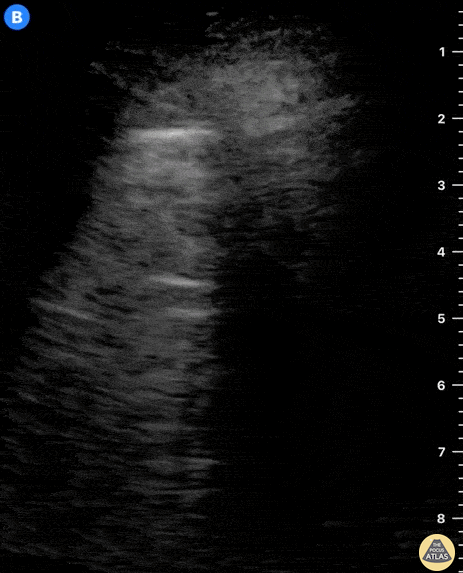

A 10-year-old patient with no medical background is brought to the ED presenting a 2-day history of dry cough and right subcostal pain. There is neither fever nor shortness of breath. A lung ultrasound was performed following physical examination which prompted the discovery of a consolidation. The probe is slid along 2 intercostal spaces revealing an oddly shaped structure with irregular edges that locates in between normal A-lines. Dr. Felipe Urriola P.